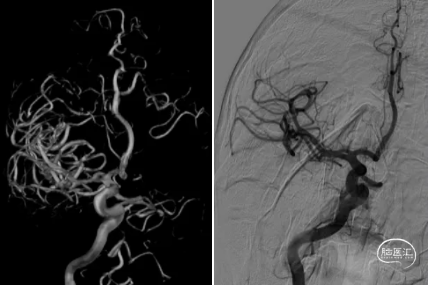

DSA:8F导引导管在4F多功能导引导管在泥鳅导丝导引下、于路图辅助下送至右侧C1段并造影,提示右侧大脑中动脉起始段充盈缺损的血栓影,可见前向血流,下干可见血流缓慢,上干可见充盈缺损的血栓影,可见前向血流,远端可见浅淡显影(如箭头所示)。

血管再通,但为什么血栓会飘浮在大脑中动脉主干呢?飘浮血栓的理论基础源于二个原因,一是分叉部,血栓可悬挂2叉上,不会造成责任血管的完全堵塞。二是血管壁本身有问题,动脉粥样硬化,内膜暴露,导致血栓粘附于此。目前的DSA检查并不能证实血管壁异常导致血栓粘附于此的理论,那么右侧大脑中动脉近端存在结构的异常呢?行3D DSA,结果证实右侧大脑中动脉存在开窗,这也解释为什么血栓会悬挂于此了。

3D DSA提示左侧大脑中动脉开窗变异。行DynaCT提示右侧基底节及颞叶造影剂渗出,调整替罗非班静脉0.2mg/h泵入,观察30分钟,复查脑血管造影提示血流分级3级,DynaCT提示渗出稍有增加。